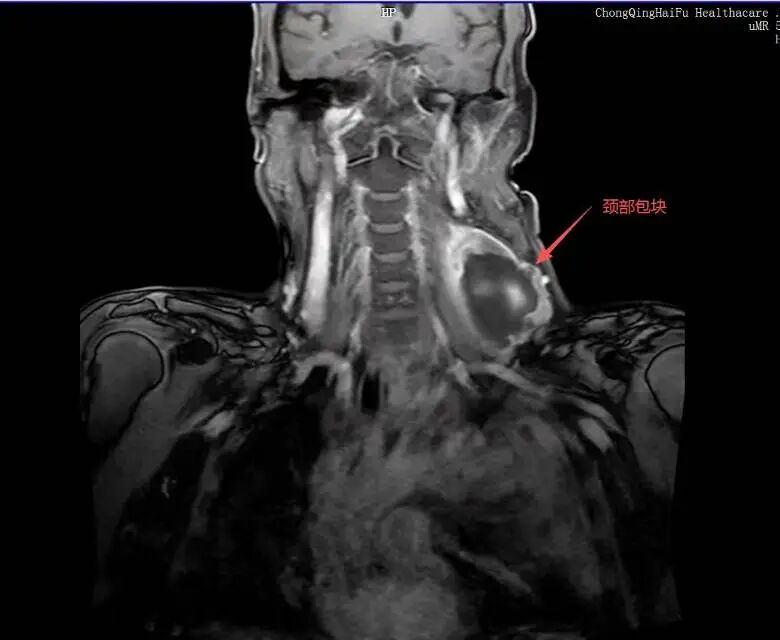

2025 年肿瘤再次复发,多处出现转移灶,2026 年颈部又长出鸡蛋大小肿块,辗转多家医院,因已是脂肪肉瘤Ⅳ期、多发转移,反复手术和化疗让身体难以耐受。

复查 MRI 显示肿瘤消融范围理想,病灶无灌注区清晰可见,远超预期。手术过程十分顺利,术后患者生命体征平稳,术后第一天,患者疼痛就明显缓解,精神、饮食都恢复良好。